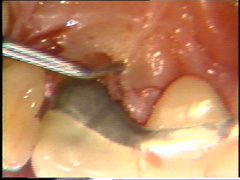

Visión palatina:

Eliminación del tejido de granulación.

Las superficies de la raíz se limpian

(raspado y alisado radicular) cuidadosamente y el tejido de granulación en los

defectos óseos (cráter) es eliminado. En la superficie bucal del segundo premolar hay

un cráter óseo y cálculo en la supericies dental adyacente.

El cálculo del segundo premolar

está unido firmemente a la superficie dental y es un proceso tedioso el

quitarlo.